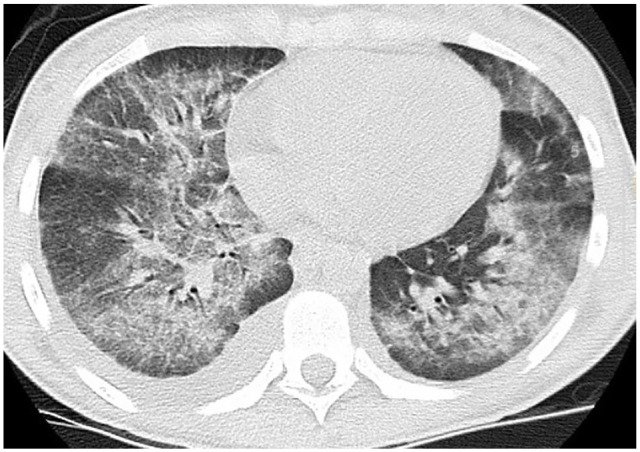

1). Initial CXR showed bilateral infiltrates and CT chest without contrast showed bilateral patchy glass patchy opacities with subpleural sparing and small right pleural effusion (Figure 3). Extensive infectious workup including sputum studies, urine, and serum studies were negative (Table 1). The patient was subsequently diagnosed with respiratory failure secondary to VALI from CBD/THC vaping. He was started on IV methylprednisone 60 mg daily for 2 days and then converted to oral prednisone 40 mg daily. He clinically improved and was discharged on room air with steroid taper to be completed in 2 weeks.